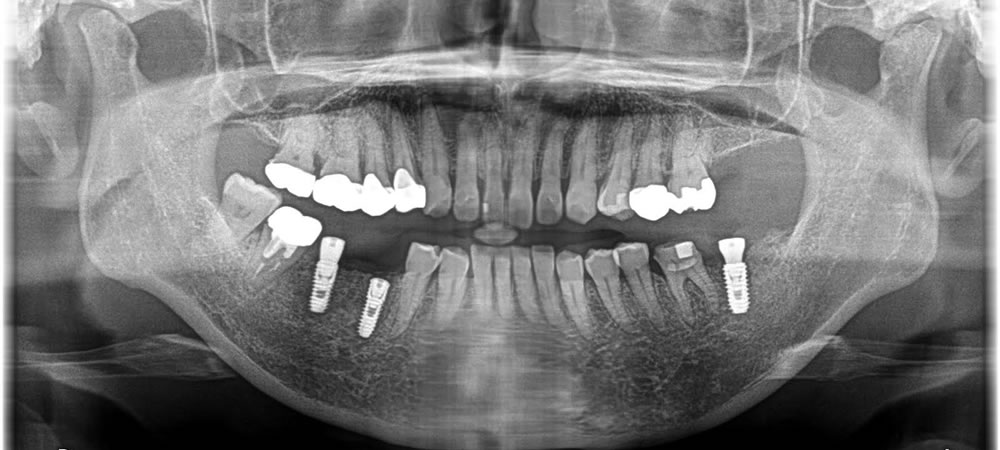

ブリッジを除去して支台歯を抜き、フィクスチャー埋入しました。骨を作る処置まで1回で行いました。その後、1週間後に消毒を行い、2週間後に抜糸を行いました。そこから人工の根と骨がしっかりとくっつくまで4ヵ月待機し、上部に歯を作成しました。

反対側は、抜歯、フィクスチャー埋入、骨造成までを1回のオペで行い、3ヵ月待機して上部に歯を作成しました。

歯を抜くと骨が一気に吸収されてしまうため、それを最小限に抑えるために骨造成もしっかりと行ったことによって、ほぼ骨の吸収がなく治療を完了する事ができました。